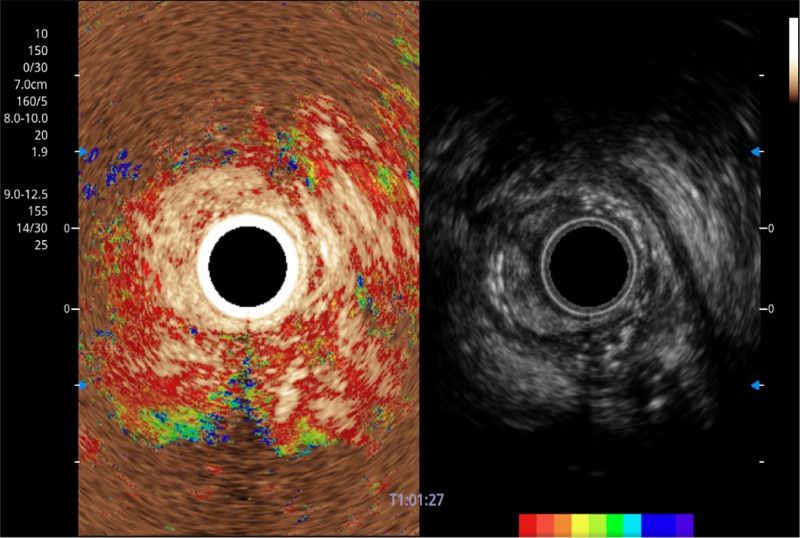

可人为将灰阶图像转变成彩色的显示方式,增强人眼对于不同回声强度的敏感度,主观上增加了图像分辨率

微米成像技术提升了对组织斑点噪声信号的抑制能力,并进一步强化边界信息,从而获得信噪比更优、边界更清楚锐利的图像

随着组织深度的变化,超声接收频率进行智能匹配跟踪,确保图像中、远场良好的穿透力以及整场一致的分辨力,从而得到均一的画质

食管内间质瘤清晰显像

清晰显示胆总管及周围血管分布